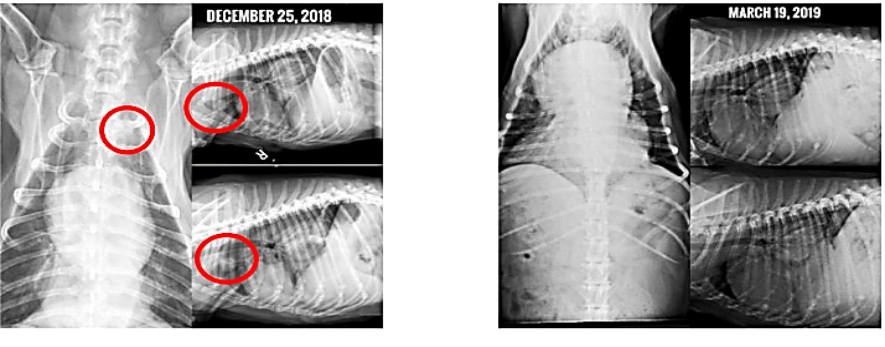

Application of Therapeutic Vaccines in the Treatment of Canine and Feline Cancers

The application of immunology and nanotechnology personalized immunotherapy in medical field has ushered in transformative changes in veterinary oncology. This paper will discuss the application of therapeutic vaccines in the treatment of canine and feline cancers. A substantial body of research indicates that therapeutic vaccines not only enhance antigen delivery but also activate robust T-cell responses and favorably modulate the tumor microenvironment. In the field of canine and feline oncology, nanoparticle-based vaccine platform has emerged as a novel strategy that improves antigen delivery and enhances cellular uptake, thereby regulating the tumor microenvironment and demonstrating significant potential in boosting immunogenicity and overall therapeutic efficacy. Concurrently, personalized vaccine offers precise identification of tumor antigens (TAs) to activate targeted T-cell responses. Unlike conventional treatments, these vaccines can be adjusted to accommodate the unique tumor features of each companion animal, substantially improving therapeutic outcomes. Early preclinical and clinical studies reveal that personalized vaccines prolong progression-free survival, reduce tumor burden, and inhibit metastatic lesions, offering new avenues for managing refractory cancers. Although challenges remain in clinical translation and large-scale application, interdisciplinary collaborations continue to advance this field, bringing unprecedented hope to the treatment of cancer in companion animals.